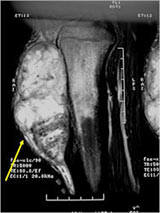

MRI:

- Mass on surface of bone

- Intermediate signal on T1 weighted images and high signal on T2 consistent with cartilage

- Usually no intramedullary invasion but may see slight erosion or saucerization of cortex

- Periosteal reaction evident on MRI as very low signal on T1 and T2 weighted images